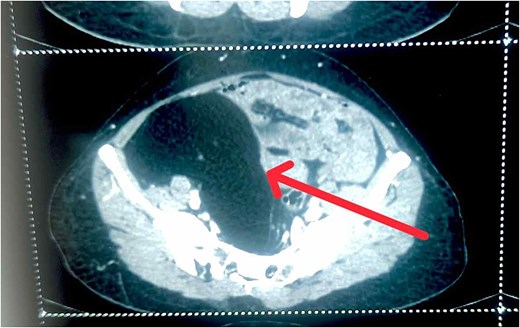

A 40-year female presented to outpatient department with 1 year history of non-specific abdominal pain. She had history of sensation of heaviness at pelvis region and increase frequency of micturition with no other urinary symptoms. She had no significant medical, surgical, and gynecological history with unremarkable family history. On physical examination, she looks healthy, consciousness. Her vitals were in normal range. Per abdominal examination: soft to palpate with mass felt ~12 × 12 cm at right lower quadrant, non-tender, and bowel sounds present. Laboratory investigation revealed complete blood count, renal function test, liver function test, prothrombin time/international normalize ratio were in normal range, cancer antigen (CA)-19.9: 32.7 μ/ml, carcinoembryonic antigen: 5.37 ng/ml, CA--125: 8.9 μ/ml. Ultrasonography of abdomen and pelvis revealed well-defined hypoechoic cystic lesion measuring 12.3 cm × 9.4 cm size with septa in right adnexa and right adnexal mass. Contrast-enhanced computed tomography (CECT) abdomen showed well-defined hypodense abdominopelvis lesion of fat density in right side measure 13.2 × 8.5 × 11.8 cm contain thin internal septa with craniocaudal extension from L4 to S5 vertebrae, abutting fundus of uterus, right ureterprximal, rt external and internal iliac vessel with no lymphadenopathy, and ascites (Fig. 1).

CECT abdomen showing well-defined hypodense abdominopelvis lesion of fat density in right side.